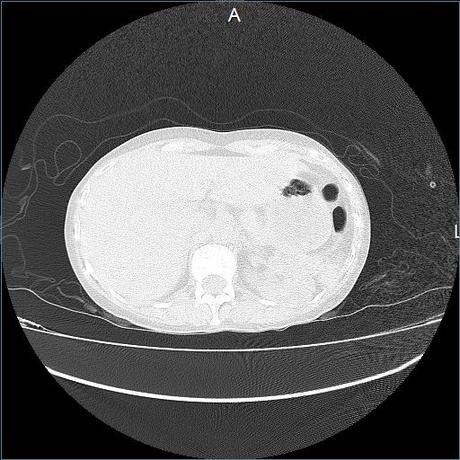

Se realiza volumen de tórax en fase simple, desde los opérculos torácicos hasta los hemidiafragmas, observándose:

El parénquima pulmonar con areas parcheadas difusas en vidrio despulido combinadas con otras areas hipodensas de baja atenuación debidas a atrapamiento aéreo y engrosamiento intersticial y zonas de fibrosis de predominio en lóbulos medios e inferiores de ambos pulmones.

En los cortes valorados de abdomen hígado, bazo y páncreas sin evidencia de alteraciones, glándula suprarrenal izquierda con imagen ovalada, bordes definidos, homogénea, mide 11 mm en probable relacion a adenoma.